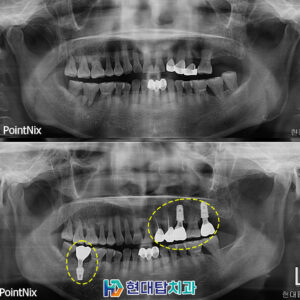

울산동구치과 망설이고 있다면 임플란트의 정의 실제 임플란트 사례 상악동 & 의식하 진정 임플란트란 의료진 소개 치아 건강은 백세 시대 속에서 삶의 질을 결정하는 핵심 요소입니다. ​ 치아는 음식물을 저작하고 부수는 저작활동을 하면서 원활한 소화가 이루어질 수 있도록 도움을 줍니다. ​ 하지만 한번 손상되거나 상실된 치아는 회복이 불가능하기 때문에 정기적인 치과검진과 더보기…

울산동구치과 임플란트의 튼튼한 사용을 위해   우리는 치아를 하루에 수백 번 이상 사용하고 있습니다. ​ 그만큼 삶의 질을 좌우하는 중요한 부분 중 하나로 음식물을 씹어서 필요한 영양분을 신체에 공급할 수 있도록 해줍니다. ​ 하지만 충치나 치주 질환, 노화, 외상, 사고 등과 같은 다양한 이유로 치아의 손상이나 상실을 맞이하게 될 수 더보기…